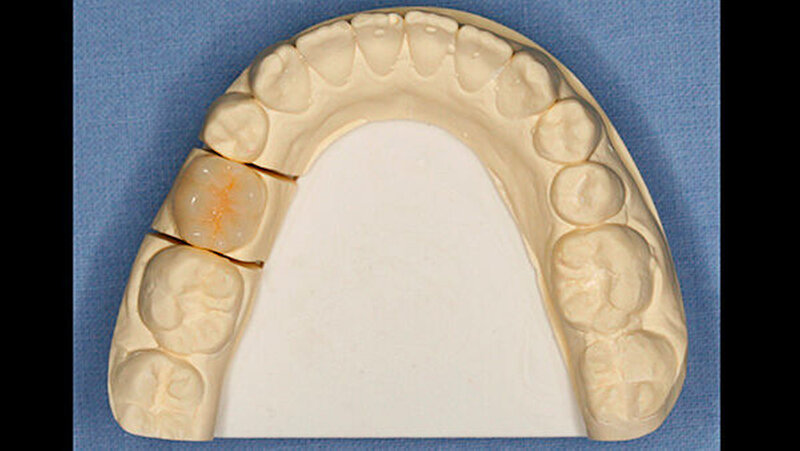

Unmittelbar nach der Entbänderung erfolgte deshalb die Abformung beider Kiefer (Aquasil Ultra Heavy und Aquasil Ultra LV, Dentsply DeTrey) sowie eine Bissnahme im Schlussbiss (Futar Fast (1:1), Kettenbach GmbH). Im Labor erfolgte die Herstellung eines Overlays aus Komposit (SR Adoro, Ivoclar Vivadent) (Abbildungen 4 bis 6), das etwa zehn Tage nach der Abformung eingesetzt wurde.